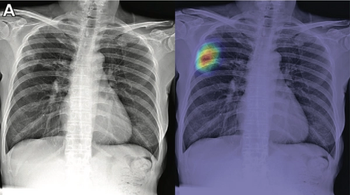

Both board-certified radiologists and radiology residents more appropriately suggested chest CT follow-up when using artificial intelligence with chest X-ray.